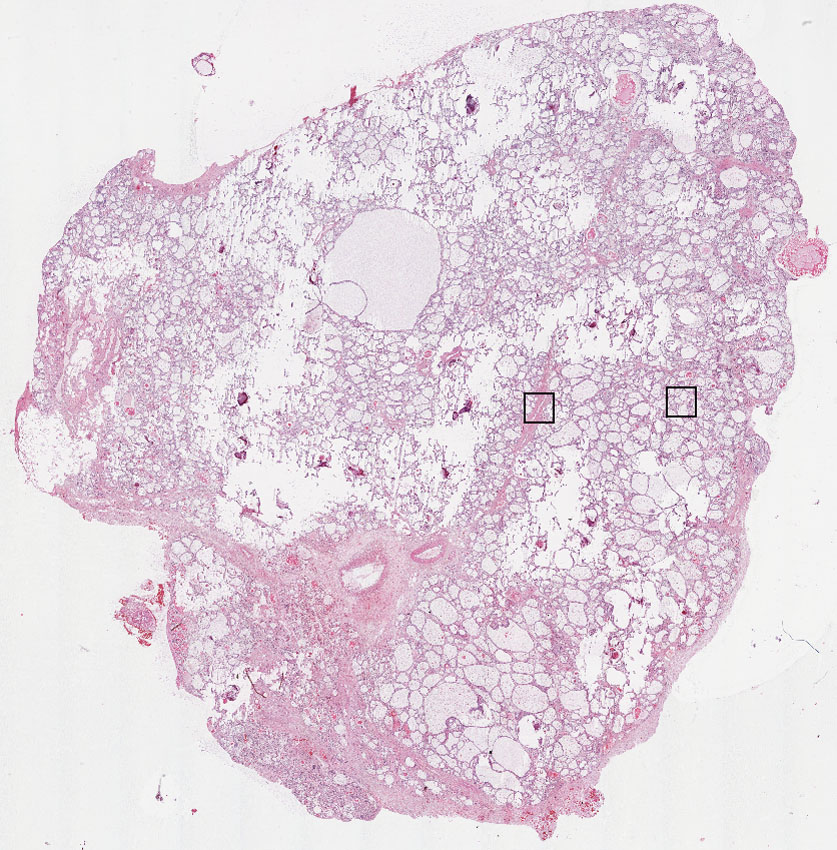

Glandular cells:

70

Endothelial cells:

15

Other cell types: